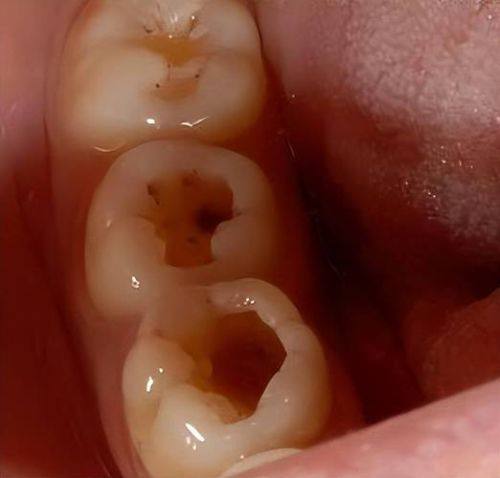

龋齿对牙齿结构的破坏是一个渐进的过程。一开始,可能只是牙齿表面出现一些小问题,比如牙齿上出现小黑点或者小斑块,这就是浅龋的表现。浅龋的时候,特别多人可能并没有明显的感觉,所以容易被忽视。但如果不及时处理,浅龋就会逐渐发展为中龋。

中龋阶段,细菌已经深入到牙齿的本质层了。这时候,牙齿可能会对冷热酸甜等刺激有一些敏感反应,吃冷热食物或者甜食的时候会觉得牙齿有点不舒服。而且,牙齿上可能会出现一些小窟窿,这些窟窿就像是一个个“陷阱”,容易藏污纳垢,让细菌更容易滋生。

如果中龋还是没有得到治疗,就会进一步发展为深龋。深龋意味着细菌已经接近或者到达了牙髓腔。这时候,牙齿上的窟窿会变得更大更深,牙齿的结构受到了重度的破坏。牙齿的坚固性大大降低,可能稍微咬一下硬一点的东西,牙齿就会出现裂纹甚至折断。